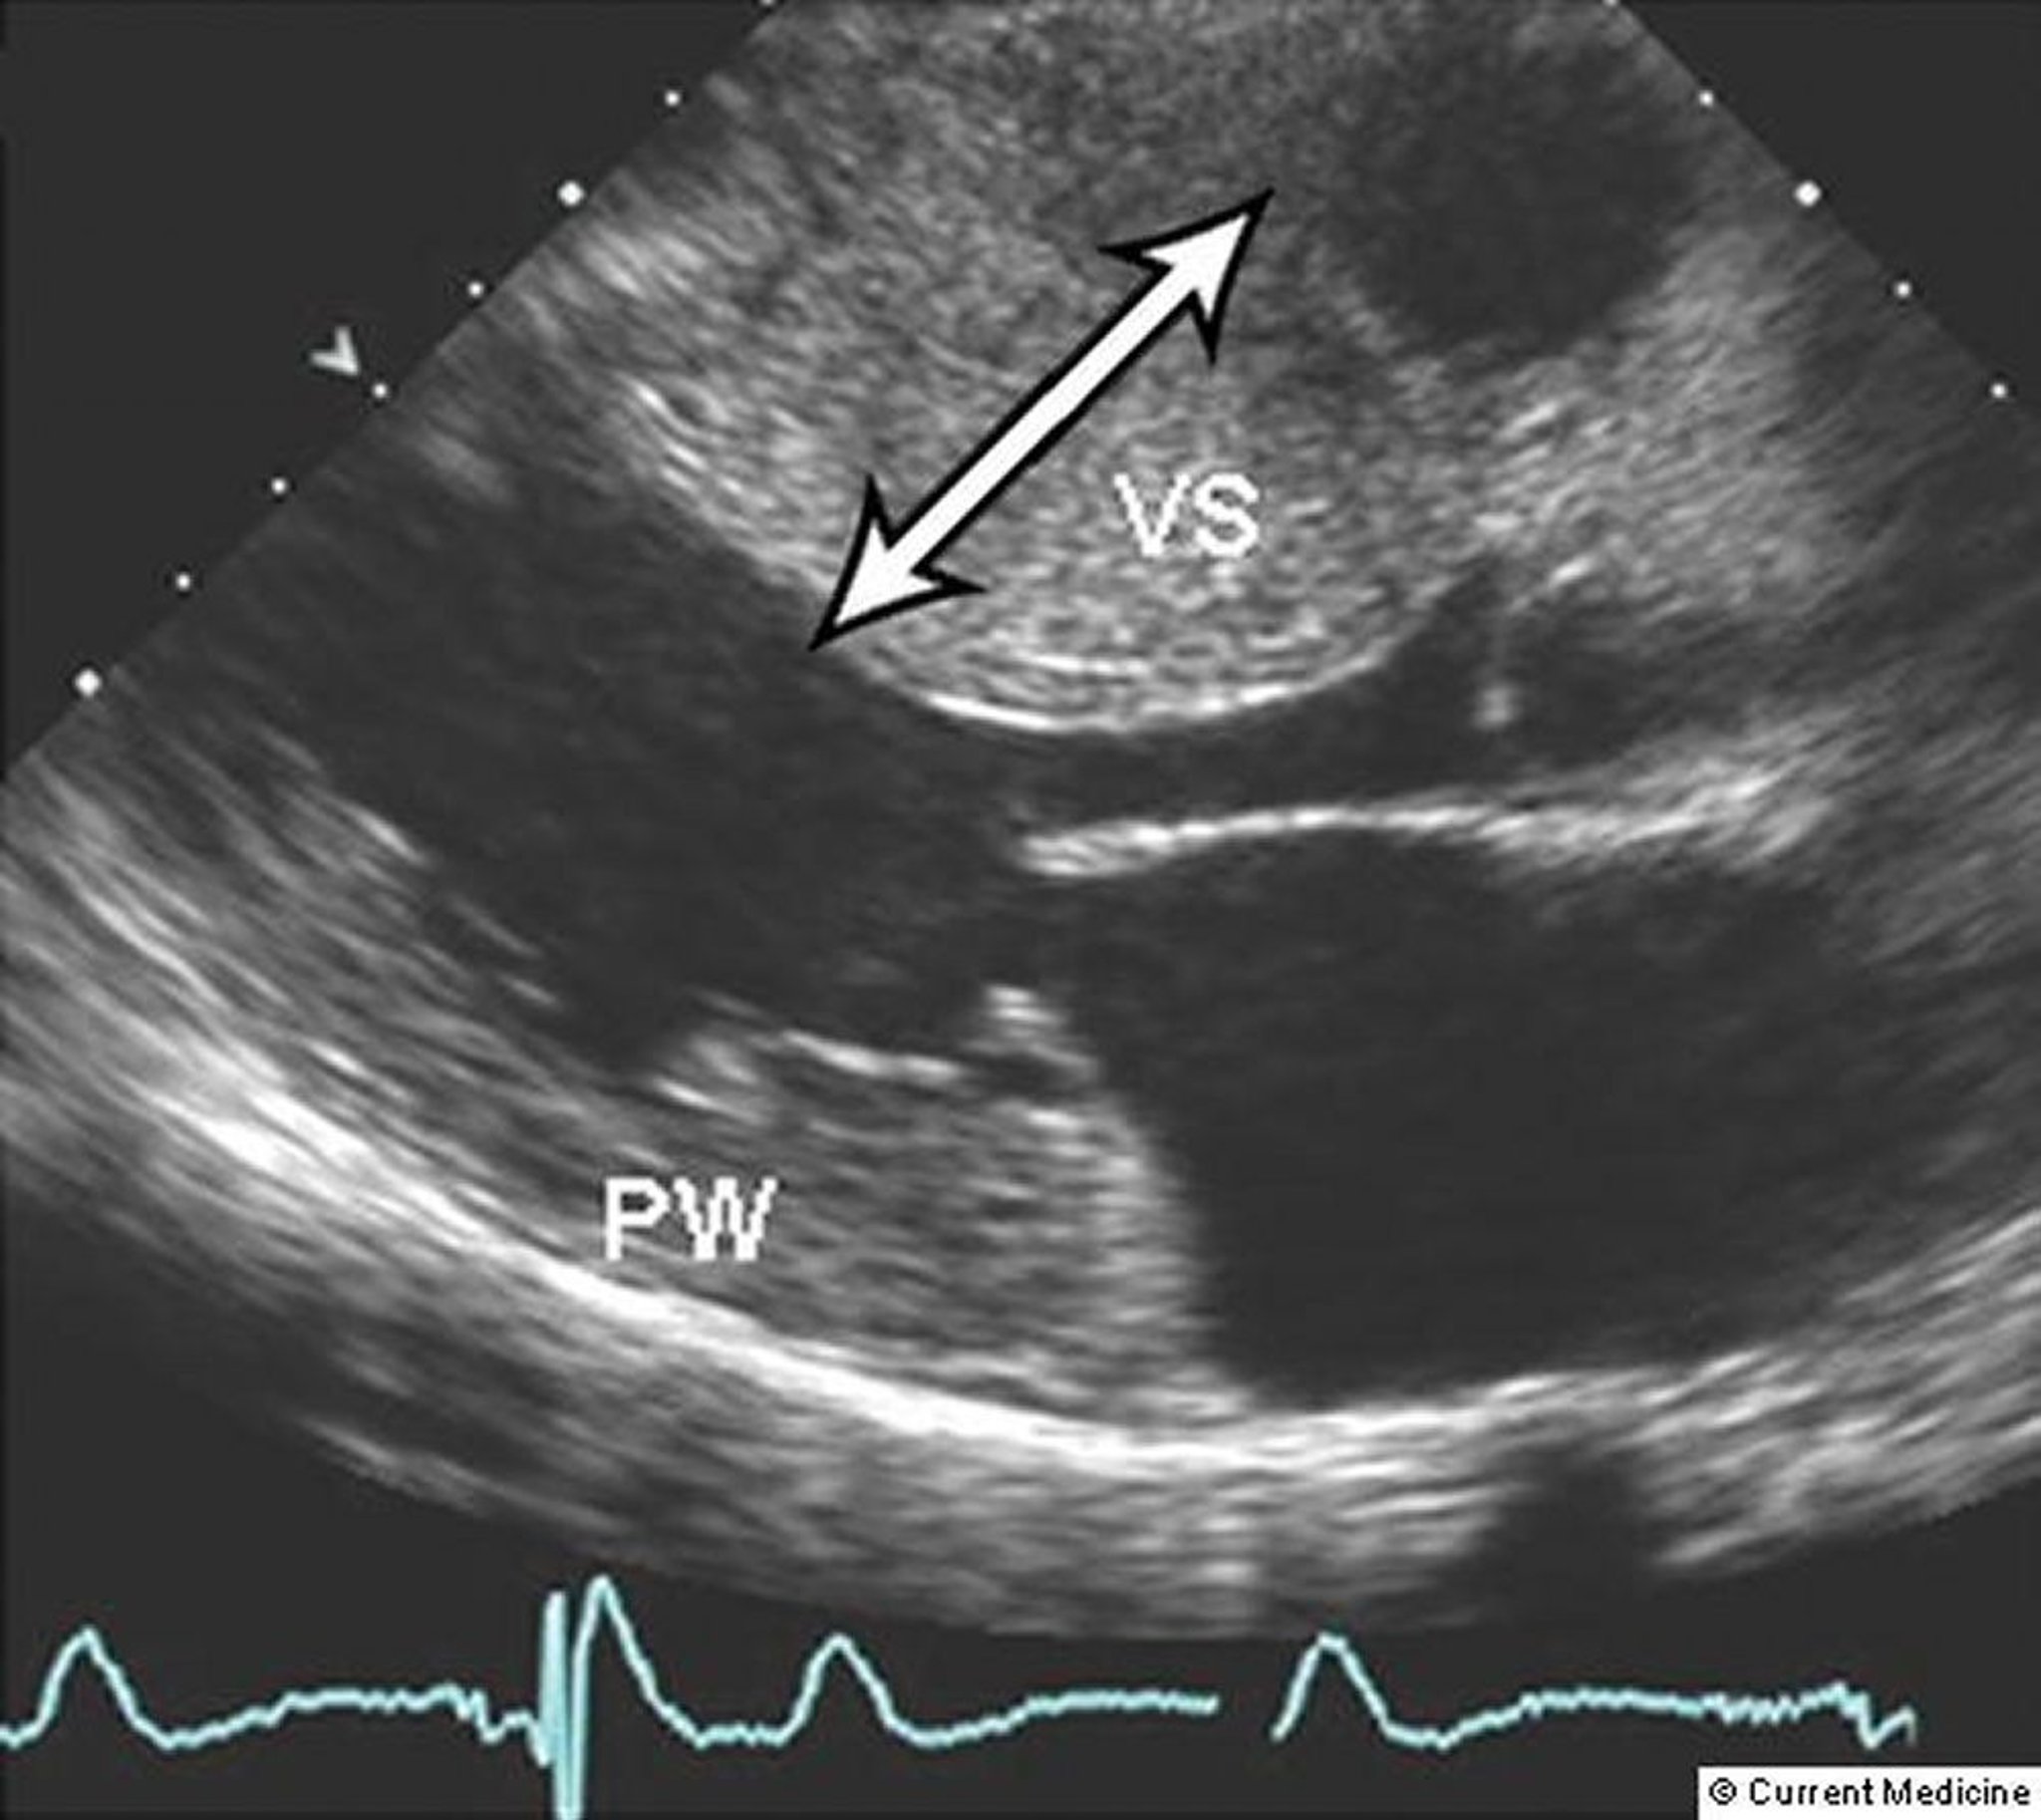

In the most common phenotype, the anterior septum and contiguous anterior free wall below the aortic valve are markedly hypertrophied and thickened, with little or no hypertrophy of the left ventricular (LV) posterior wall. Sometimes isolated apical hypertrophy occurs; however, virtually any asymmetric pattern of left ventricular hypertrophy can be observed, and in a small minority of patients even symmetric hypertrophy has been noted.

Two-dimensional Doppler echocardiography can differentiate the forms of cardiomyopathy (see figure Forms of Cardiomyopathy) and quantify the severity of hypertrophy and degree of outflow tract obstruction. These measurements are particularly useful for monitoring the effect of medical or surgical treatment. Midsystolic closure of the aortic valve sometimes occurs when outflow tract obstruction is severe. Ambulatory 24-hour monitoring is recommended during the initial evaluation and every 1 to 3 years to assess risk of sudden cardiac death and help guide treatment of arrhythmias (1).